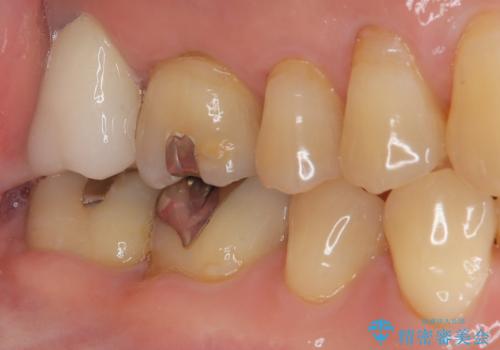

外側に飛び出している歯 部分矯正を用いた奥歯の補綴治療

- 奥歯のむし歯治療を希望して来院された患者様です。

上顎の奥歯は、左右ともに外側に転位しており、特に右上はむし歯の範囲が広く、根管治療も必要な状態でした。

上顎左右の歯をアンカースクリューを用いた部分矯正により位置を修正し、オールセラミッククラウンにて補綴治療を行うこととしました。